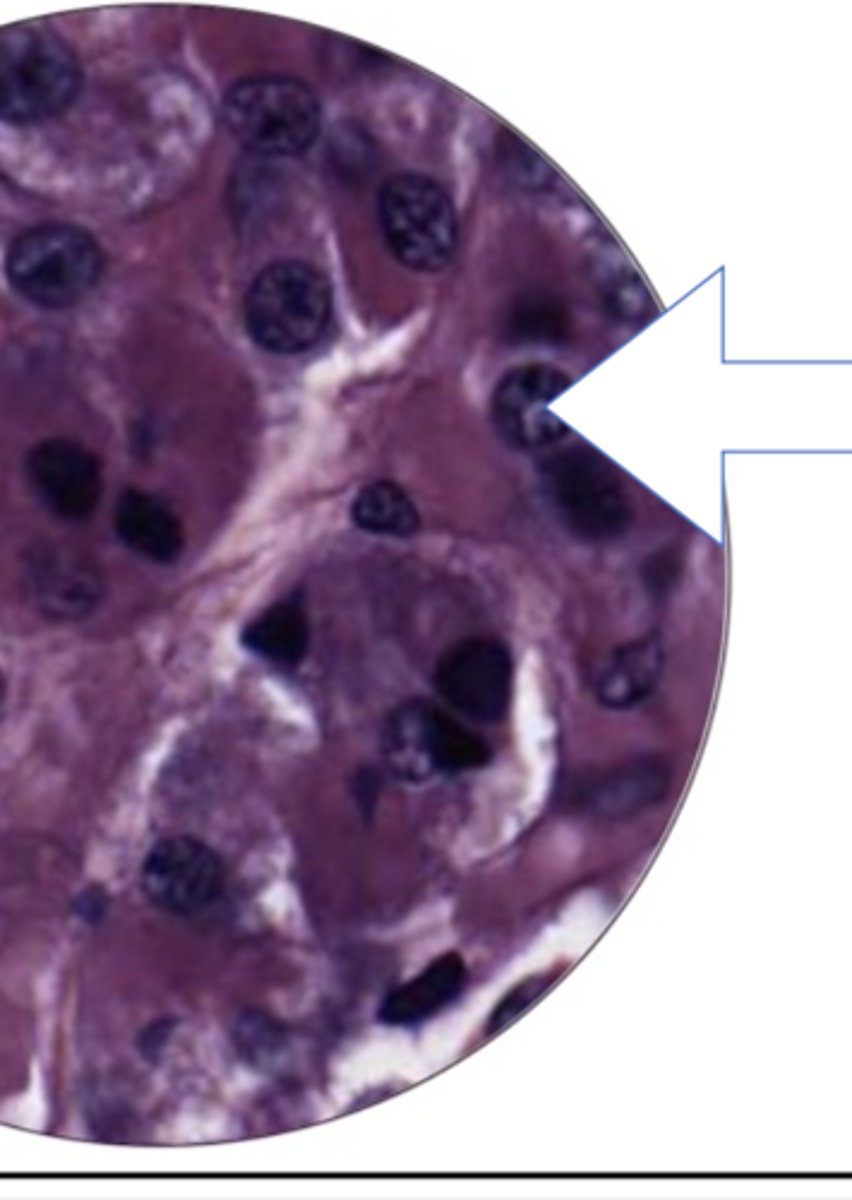

seminiferous tubule

leydig cells

sperm cell